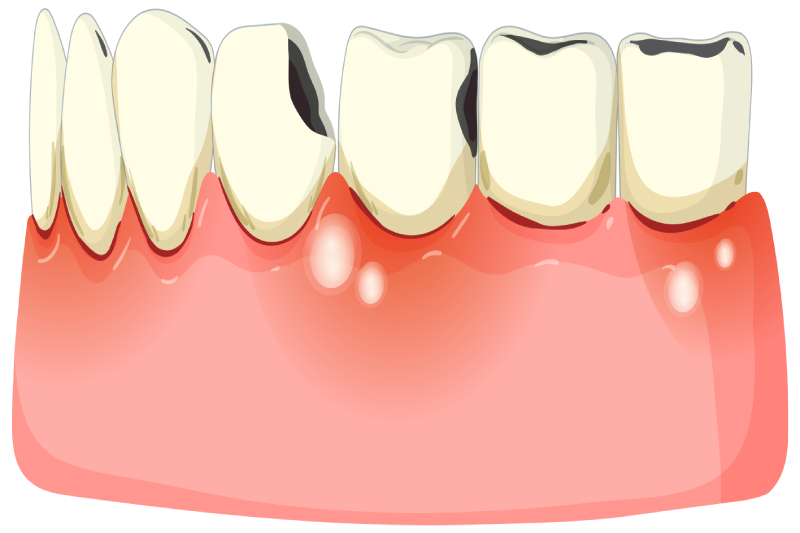

Here are some mouth problems that can happen:

- Red gums that hurt

- Bleeding when you brush

- Bumps on your gums

- Teeth that feel loose

- More cavities

Pregnancy Gingivitis – Red, Puffy Gums

Gingivitis means your gums are sick. Your gums may look red, feel puffy, and bleed when you brush.

Pregnancy Tumors – Don’t Worry, They’re Not Cancer

Some pregnant women get bumps on their gums. Doctors call these “pyogenic granulomas” but many people call them “pregnancy tumors.”

These bumps:

- Look red and raw

- Bleed easily

- Usually show up in month 2

- Often go away after your baby is born

If a bump bothers you, your dentist can help remove it.

Tooth Decay – Stopping Cavities

When you are pregnant, you might:

- Eat more sweet foods

- Have a dry mouth

- Feel too tired to brush well

This can lead to more cavities.